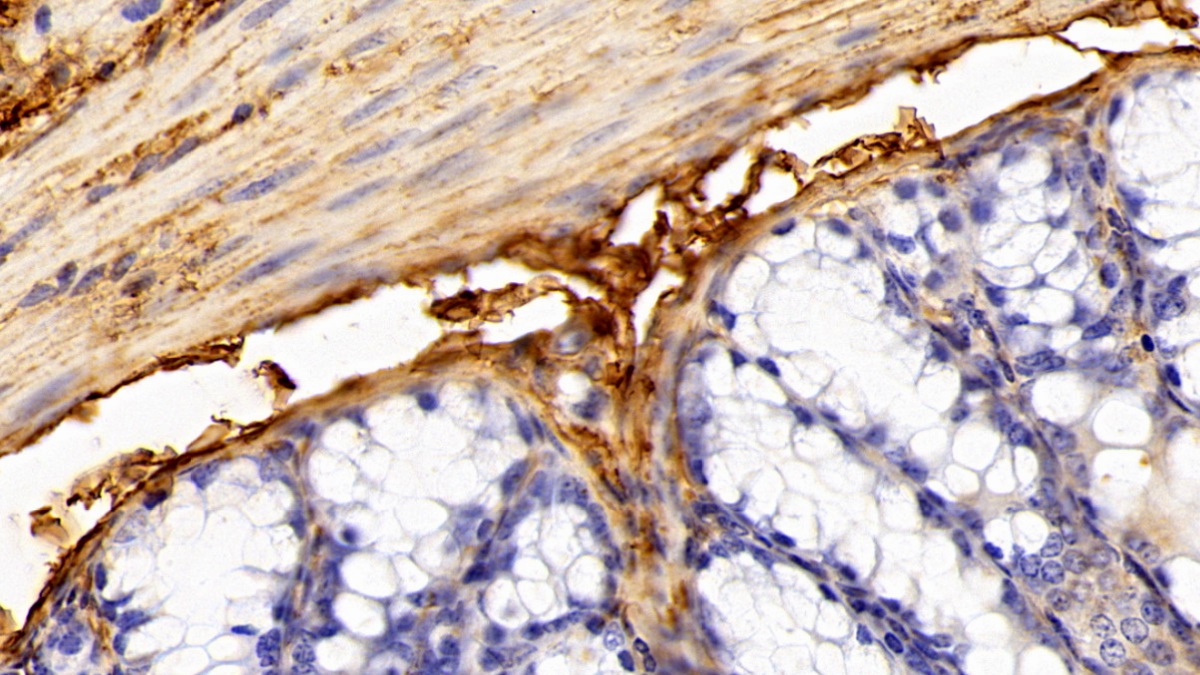

Использование высококачественных первичных антител является неотъемлемым условием получения точных и воспроизводимых результатов в современных научных исследованиях. Например, в рамках онкологического исследования удалось достоверно идентифицировать экспрессию белка PD-L1, что сыграло ключевую роль в оценке потенциальной эффективности иммунотерапии. Применение надежных антител обеспечило стабильность сигнала и высокую специфичность детекции, что позволило получить данные, пригодные для публикации в рецензируемых научных изданиях.